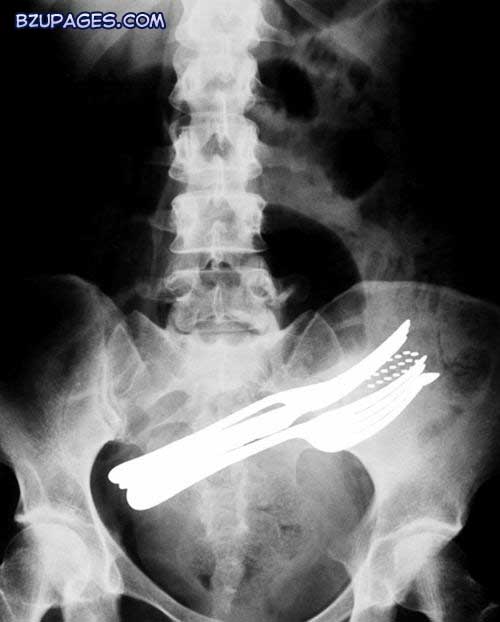

From broken bones to disease the X-Ray is one of the most useful medical advancements in history. But as these images show they can also reveal some of the most gruesome and bizarre results. Here, an X-ray shows the abdomen of a patient that has swallowed two forks, a ballpoint pen and a toothbrush. The items are located in the intestine